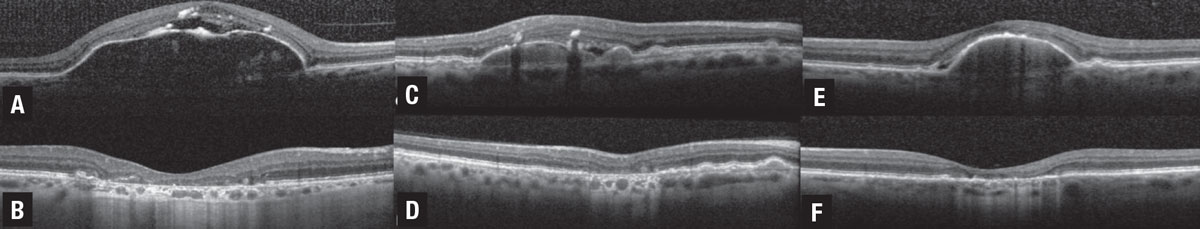

Mechanical strain from confluent drusen can also result in the appearance of SRF. In these cases, when confluent drusen are accompanied by subretinal spaces that appear filled with fluid, distribution of the fluid in the area between adjacent drusen may indicate that the group of coalescent drusen creates mechanical strain on the outer retinal layers, pulling the sensory retina away from its position.3 A 2020 study examined three different patterns of subretinal fluid in non-neovascular AMD that progress to collapse and atrophy:1

- fluid at the apex of a large drusenoid pigment epithelial detachment;

- fluid at the crypt between confluent drusen; and

- low-lying drape of fluid over confluent drusen (Figure 2). As a result, distinguishing between fluid that’s secondary to neovascular or non-neovascular processes is critical for making appropriate treatment decisions and avoiding unnecessary anti-VEGF therapy.

![]() |

| Figure 2. Three cases of non-neovascular age-related macular degeneration illustrating drusenoid pigment epithelial detachment (PED) and drusen associated with three different patterns of subretinal fluid (SRF) that progress to collapse and atrophy.1 A) Spectral-domain optical coherence tomography illustrates drusenoid PED with crest of SRF associated with an acquired vitelliform lesion and focal retinal pigment epithelium thickening, including intraretinal hyper-reflective foci. B) At the five-year follow-up visit, the drusenoid PED is collapsed with development of complete RPE and outer retinal atrophy (cRORA). C) SD-OCT illustrates drusenoid PED with SRF located at the angle or crypt of the PED. D) At the 10-month follow-up visit, the PED is collapsed with progression to cRORA. E) SD-OCT illustrates drusenoid PED with low-lying drape of SRF. F) At the seven-year follow-up visit, the drusenoid PED is collapsed with progression to cRORA. (Figure courtesy Assaf Hilely, MD. Reprinted with permission BMJ Publishing Group). |